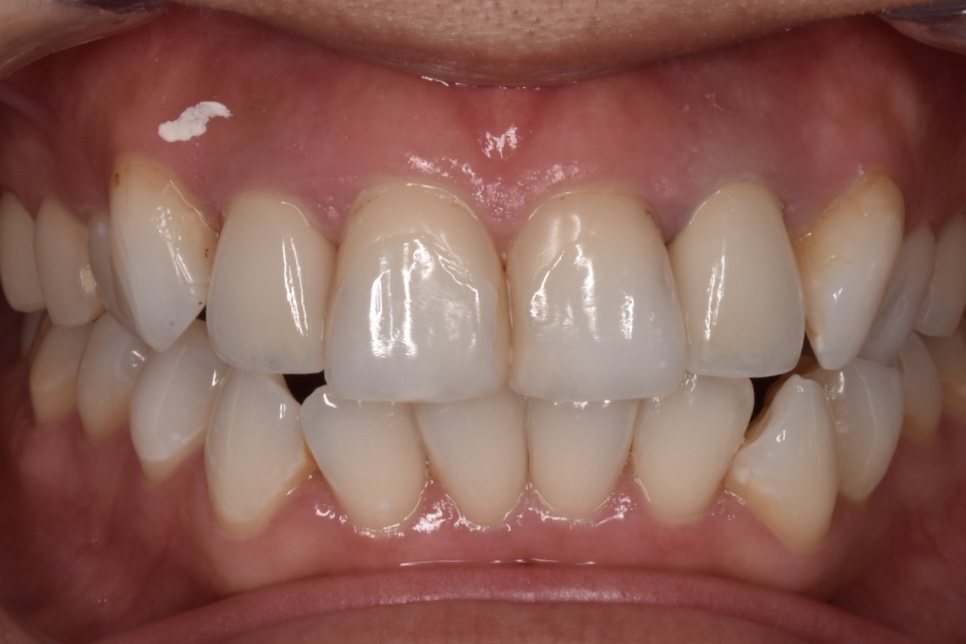

モニター様④

上の前歯(左右側切歯)2本のやりかえです。*ダイヤモンド匠プラン